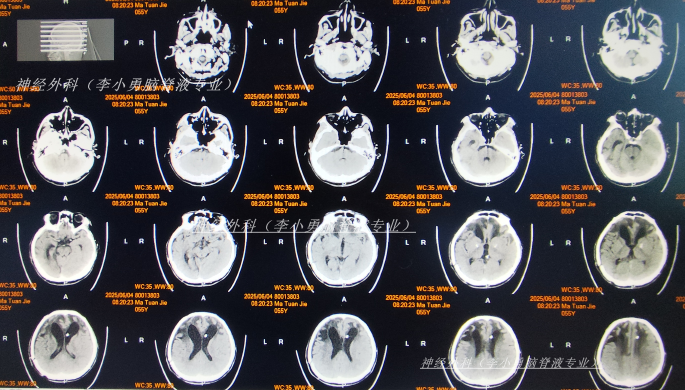

继续治疗1月半脑脊液各项化验达标后于2025年6月3日,进行了脑室腹腔分流术(图-21)。

图-21:2025年6月4日头颅CT

2025年6月17日(李小勇脑脊液专业治疗4月余)出院,出院时:意识进一步好转虽反应慢些,但体温正常,在搀扶下能慢慢走路,饮食变正常(图-22);颅内感染和肺部感染均变好。

图-22:2025年6月17日出院时